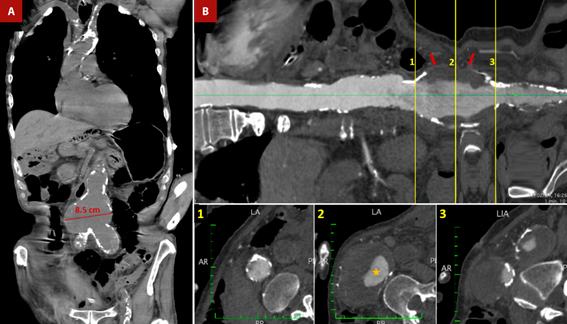

Figure 3 Shaggy aorta and abdominal aortic aneurysm. An 84-year-old male patient was admitted to the emergency room with severe diffuse abdominal pain. Medical history included hypertension, diabetes mellitus, chronic kidney disease and senile dementia. A. Non-contrast thoracoabdominal CT - coronal section. Severe calcification of the aorta is observed, predominantly in the aortic arch and abdominal aorta. Also, there is an aneurysmal dilatation of the infrarenal aorta with a maximum diameter of up to 8.5 cm. B. Longitudinal reconstruction of the aorta. The transverse sections at the level of the abdominal aortic aneurysm demonstrate the calcification of the abdominal aneurysm wall, along with the presence of an extensive mural thrombus (red arrows) and a reduced luminal diameter (orange star). Mesenteric ischemia was suspected, with the emboligenic source coming from complex atheromatous aortic plaques or abdominal aortic aneurysms. The patient was admitted to the operating room for an exploratory laparotomy. However, the patient died during the operative procedure.